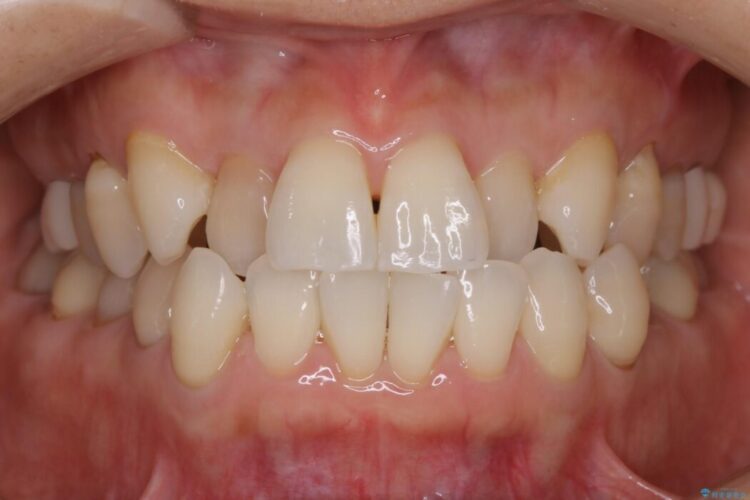

前歯のガタつき、噛み合わせの不調を改善したいとご来院されました。

気になっていたガタつきも改善され、患者様にはご満足いただけました。